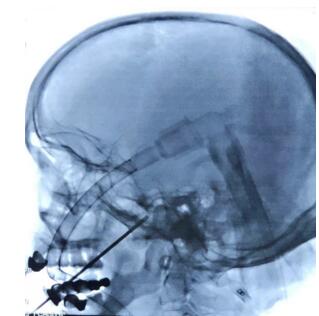

文世宏主任手術(shù)中

在征得患者及家屬同意,做好充分的術(shù)前準(zhǔn)備后,文世宏主任成功為患者施行了手術(shù)。該術(shù)式雖操作簡單,但最大的難點(diǎn)便在于“穿刺”這一環(huán)了,這近乎于“盲穿”,對術(shù)者的操作技能要求極高!然而憑借敏銳的觀察力與準(zhǔn)確的判斷力,文世宏主任輕輕松松就完成了這一操作,被同事笑稱為“文一針”!

在C形臂引導(dǎo)下經(jīng)嘴角外側(cè)穿刺進(jìn)入卵圓孔,將球囊導(dǎo)管送至半月神經(jīng)節(jié),充盈球囊,壓迫數(shù)分鐘,破壞神經(jīng)傳導(dǎo),達(dá)到治療目的。